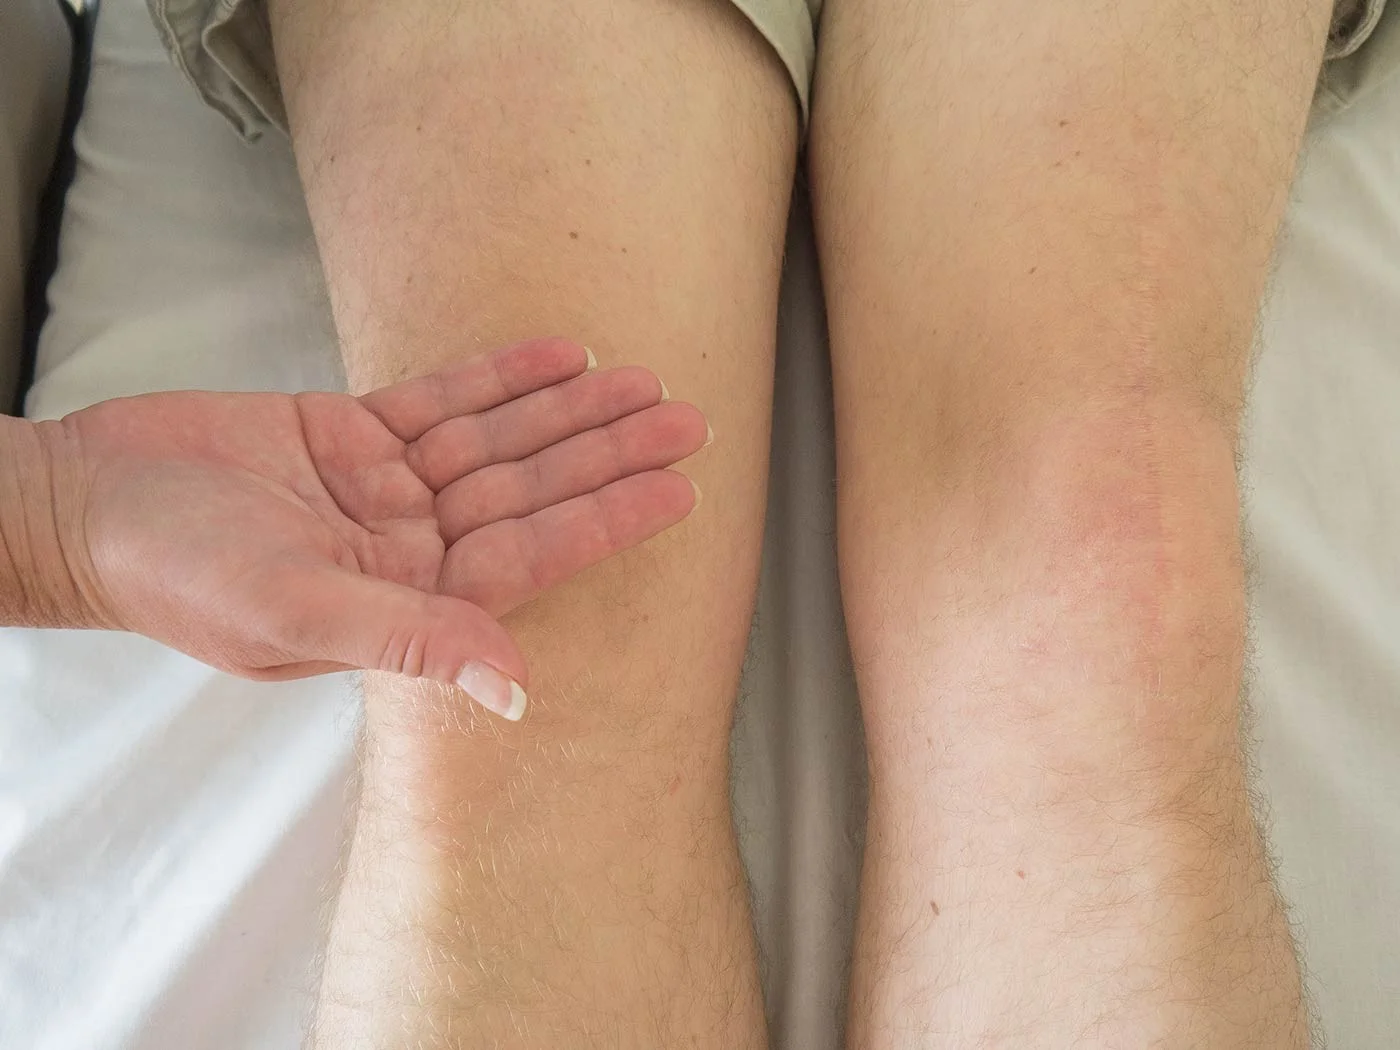

| Look | Compare both limbs, Skin, Muscle bulk, bony landmarks, hair distribution | Assess symmetry, signs of trauma, inflammation, muscle atrophy, structural changes | Visual examples - Skin, Muscle, Bone, Joint: ![]() ![]() ![]() ![]() ![]() ![]() | Swelling, scars, discoloration, hair changes, muscle wasting, bony protrusions, angulation, redness |

| Back of knee | Assess for posterior aspect abnormalities, such as Baker’s cyst | Posterior aspect: ![]() | Swelling, tenderness, masses in the popliteal fossa | |

| Feel | Tenderness (General, Localized): Quadriceps, Patella, Patellar tendon, Tibial tuberosity, Origin, and insertion of collateral ligaments, ACL, MCL | Identify areas of pain and inflammation in relevant structures | Tenderness - General: Tenderness - Localized: Medial Structures (Tibial Tuberosity, Joint Line, Medial Tibial Condyle, Patella, Medial Femoral Condyle, Joint Space, MCL): ![]() Lateral Structures (Quadriceps, Patella, Tibial Tuberosity, Head of Fibula, LCL, Lateral joint line): ![]() | Localized pain upon palpation |

| Joint-line tenderness, medial and lateral | Assess for meniscal or collateral ligament pathology | Joint lines: ![]() | Pain upon palpation along the joint line | |

| Temperature: compare R & L, distal & proximal | Identify signs of active inflammation or infection | Temperature Comparison: ![]() | Increased warmth compared to contralateral side or unaffected areas | |